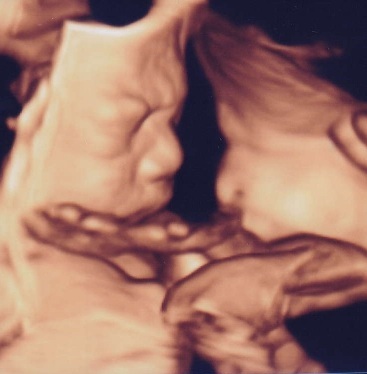

エコーはFujifilmの最新型の機械を導入しました。動く赤ちゃんを立体的にみられる4Dエコーも全例で実施します。赤ちゃんの位置や向きによっては上手くお顔が見えないことや、赤ちゃんによってはなぜかいつも背中しかみせてくれない子もいます。その点はご了承ください。

当院での4Dエコー画像例(患者様には掲載について了承をいただいております。)

25週 男の子